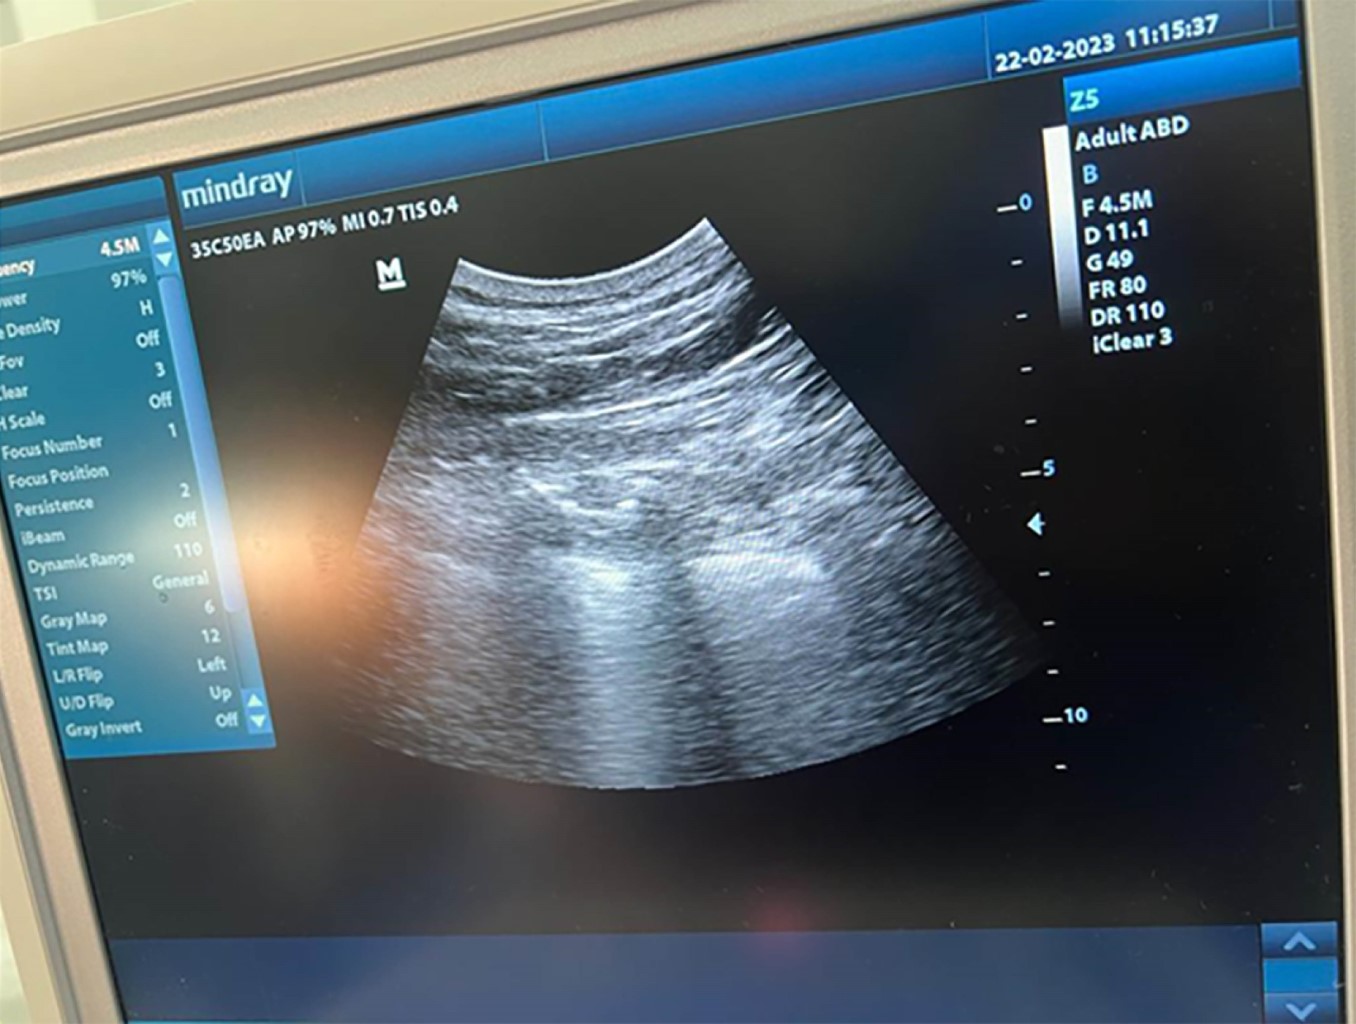

Se utilizó monitoreo no invasivo con oximetría de pulso, presión arterial no invasiva, electrocardiograma continuo y monitoreo del índice biespectral. Con el paciente en decúbito lateral, se procedió a realizar de forma ecoguiada bloqueo paravertebral derecho a nivel de la sexta vértebra torácica (Figura 1) administrando ropivacaína a 0.75% 75 mg, con un volumen total de 10 mL y bloqueo del nervio intercostal derecho, sobre el noveno arco costal, adyacente a éste se administró de igual forma ropivacaína a 0.75% 7.5 mg, con un volumen total de 10 mL (Figura 2).

Figura 1